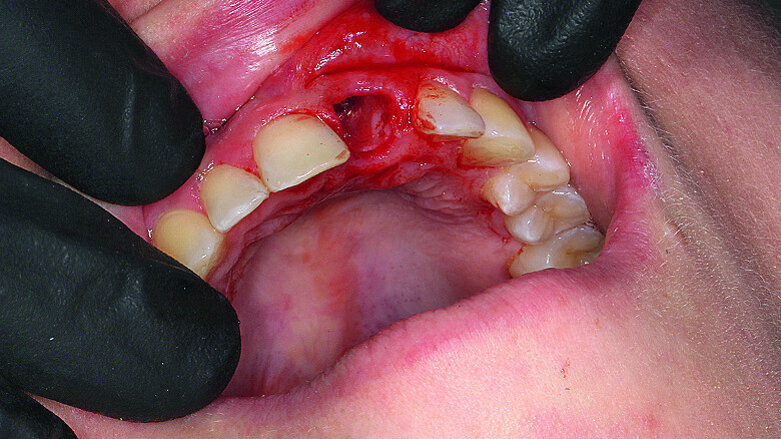

Fig. 1: Single-tooth exposure of tooth #21 after recurrent marginal gingivitis. Owing to the initial diagnosis of extensive resorption, the tooth could not be preserved.

Fig. 2: Initial situation: tooth #21 exhibited marginal redness of the gingiva that bled when probed.

Fig. 7: Gentle extraction preserving the vestibular lamina.

The female patient, born in 1989, came to my practice with problems at tooth #21 caused by a childhood trauma. The gingival margins were reddened and bled when probed. The intraoral radiograph showed posttraumatic resorption of the root, and the tooth could therefore not be preserved (Figs. 1 & 2). The tooth was to be replaced by an implant with an all-ceramic crown immediately after extraction. To plan the procedure, a 3-D radiograph (Orthophos XG 3D, Dentsply Sirona) was taken. It was important to assess the available horizontal and vertical bone and evaluate apical osteolytic processes after the failure of endodontic treatment and in the region of the crestal bone due to progressive dentinal resorption. The integrity of the vestibular lamina was preserved, and there was sufficient apical bone to allow immediate implantation with immediate loading (Fig. 3).

When extracting tooth #21, it was important to preserve the vestibular lamina to allow immediate implantation. For this reason, the Sharpey’s fibres were carefully severed with a periotome, and the tooth was gently removed (Fig. 7). The tooth had pronounced dentinal resorption, confirming the previously made diagnosis (Fig. 8). The SiroLaser Blue (Dentsply Sirona) with a wavelength of 970 nm was used to disinfect the alveolus. An OsseoSpeed EV 4.8–15 mm implant (Astra Tech Implant System, Dentsply Sirona) was inserted immediately using a surgical guide (SICAT OPTIGUIDE, SICAT; Fig. 9). At > 35 Ncm, sufficient primary stability was achieved.

Given the great aesthetic demands and the need for rapid results, thorough consideration must be given to the options available for treating anterior teeth. In my view, conservation by means of conventional techniques was not possible in this case owing to the comprehensive and advanced internal resorption of tooth #21 due to previous trauma. Upon extracting this tooth, it was particularly evident that it was not worthy of conservation (Fig. 8). The young age of the female patient and the integrity of the adjacent teeth meant that a bridge was ruled out as an alternative. In light of the favourable anatomical situation with fully conserved vestibular bone lamella, immediate implantation was the optimal treatment option for improved conservation of the bundle bone and, along with it, the hard and soft tissue. The fixed provisional crown supported the soft tissue, was aesthetically pleasing and offered the patient a highly satisfactory solution. Moreover, the digital workflow offered the patient additional comfort (impression without a tray).